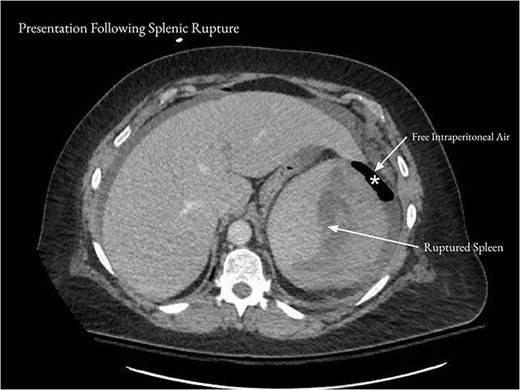

On the day following discharge, the patient presented to the emergency department complaining of sudden worsening of her abdominal pain. She reported that she had been sitting on her couch when she felt a “pop” followed by severe left upper quadrant pain, chills, and nausea. On examination, heart rate was in the 110 s, and there was mild abdominal distention and moderate tenderness to palpation over the left upper quadrant. WBC was 12.2 × 103/μl, hemoglobin was 9.6 g/dl, and hematocrit was 26.7%. CT of the abdomen and pelvis showed a new subcapsular hematoma of the spleen, measuring 7.2 cm in thickness, with adjacent subcapsular gas (Fig. 2). There was moderate free intraperitoneal air.

After the patient represented with acute worsening of abdominal pain, CT of the abdomen and pelvis showed a 7.2 cm subcapsular hematoma of the spleen (arrows) and moderate free intraperitoneal air (asterisk).